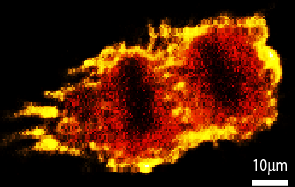

Illuminating tumour micro environments

Advanced technical imaging capabilities and research projects supported by MWC are helping to identify new prognostic and diagnostic biomarkers to advance potential therapeutic tar

read the full story

New imaging improves our understanding of the immune system

Maurice Wilkins Centre researchers have used novel imaging technology to reveal the structure and inner workings of entire lymph nodes, core components of the body’s immune system.

read the full story

Mapping microscopic worlds

Maurice Wilkins Centre researchers have used unique microscopic imaging techniques to peer into the three-dimensional structure of blood vessel networks – and new computational tec

read the full story